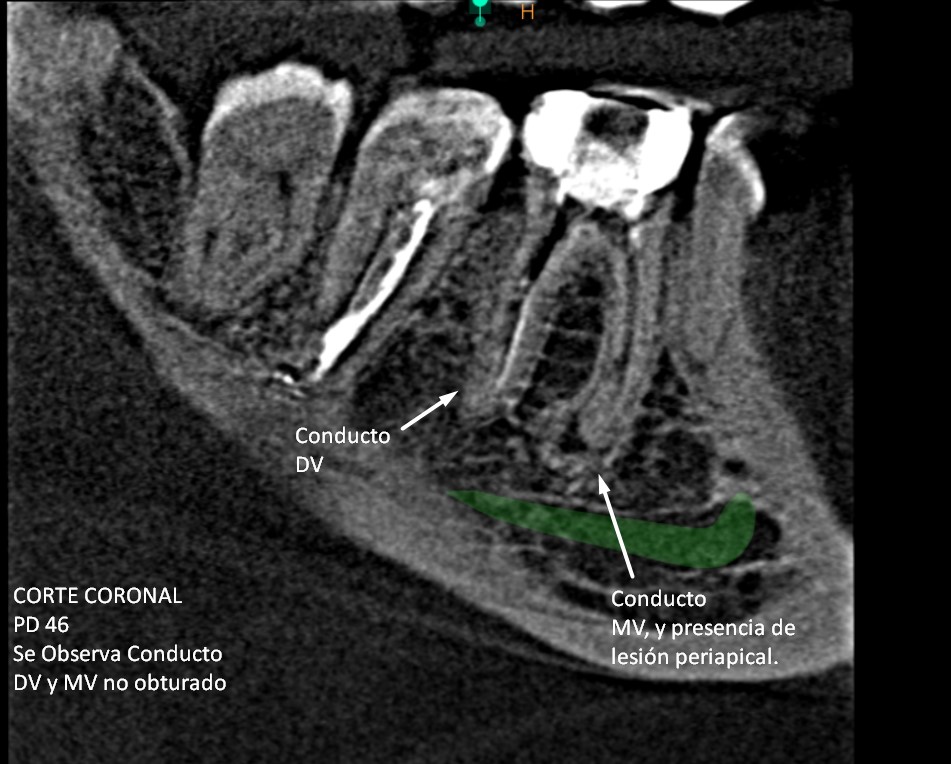

​En el resultado de la tomografía se pudo observar la presencia de Pd 47 y 46 con tratamiento de conducto (ver imagen 1) de los cuales a través de las diferentes vistas (transaxial, axial y tangencial) se pudo comprobar que la pieza dentaria 46 presenta lesión periapical (ver imagen 2), y que cuenta con 4 conductos dentarios de los cuales 2 no se encuentran obturados: el conducto Disto-Vestibular y Mesio-Vestibular. Ver imagen 3.